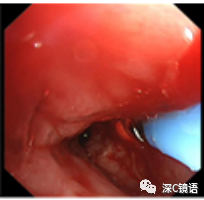

医疗方面:目前,我科室能开展呼吸内镜相关诊断与治疗技术,具体如下:诊断技术包括经支气管镜冲洗术、灌洗术、刷检术、活检术、针吸活检术、环形超声以及内科胸腔镜等;治疗技术包括球囊扩张术、支架植入术、高频电凝术、高频电圈套治疗、激光治疗、冷冻治疗、局部注药治疗等。秉承“患者所需,医者所为”的宗旨,为肺部感染、肿瘤、气道异物、不明原因胸腔积液,尤其是气道结核的患者,提供综合诊治方案。